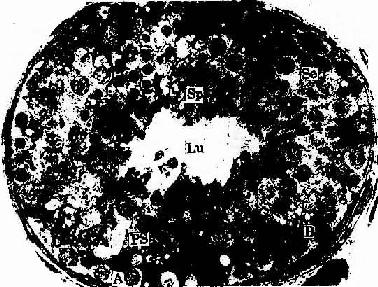

成人的生精小管(seminiferous tubule)长30~70cm,直径150~250μm,中央为管腔,壁厚60~80μm,主要由生精上皮(spermatogenic epithelium)构成。生精上皮由支持细胞和5~8层生精细胞(spermatogenic cell)组成。上皮下的基膜明显,基膜外侧有胶原纤维和一些梭形的肌样细胞(myoid cell)。肌样细胞收缩时有助于精子的排出(图16-2)。

人生精小管扫描电镜像

图16-2 人生精小管扫描电镜像 ×180

Lu生精小管管腔 SE生精上皮IT间质